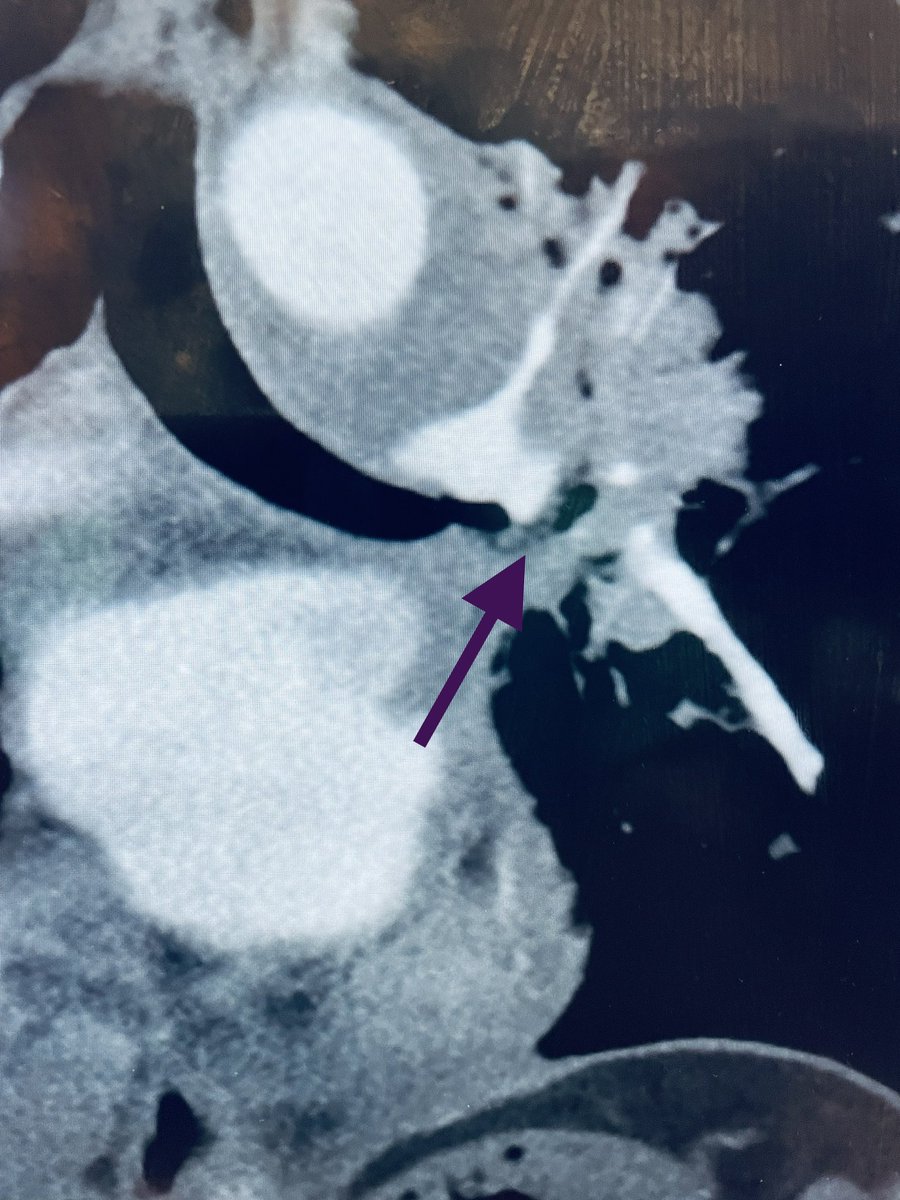

New study @AnnalsofIM bit.ly/2Km3KYu by @DrTalenfeld @WeillCornell: Percutaneous ablation for T1a #renalcancer has similar 5-year survival rates to radical nephrectomy but with far fewer 30-day complications and less #kidneyfailure.